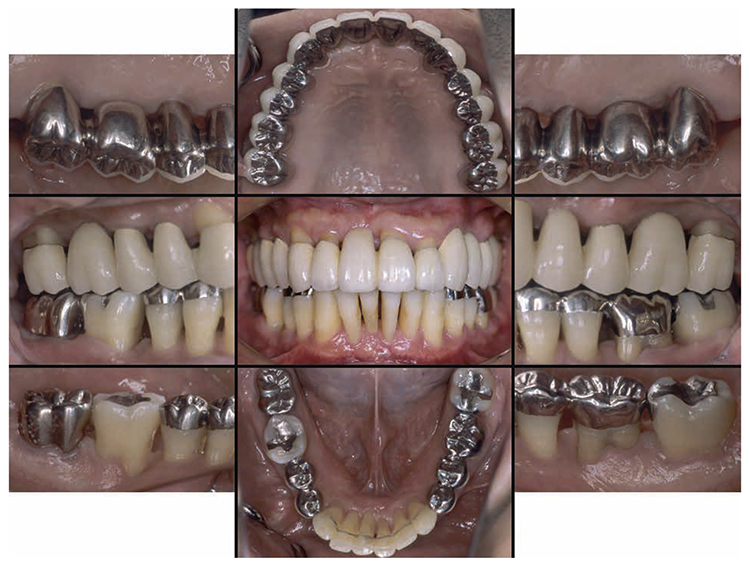

7) Reevaluation testing (December 2003)

At the reevaluation examination after treatment to restore oral function, the color of gingiva was pink, and with prosthetics, intraoral harmony was replicated esthetically and functionally. (Fig.6a). The average PD across the entire jaw was 2.1mm, maximum PD was 4.0mm, the ratio of PD of 3mm or below was 99.3%, no BOP was found and the condition of the periodontal tissue was stable (Fig.6b). In the X-ray, continuity of the alveolar hard line was replicated and the sequence of bone trabeculae was normal, and therefore, the patient transitioned to the SPT phase (Fig.6c).

Fig 6a

(Fig.6a) Intraoral photo after completion of restoration of oral function was completed(2013.4)